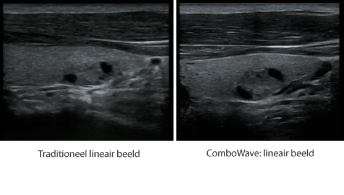

Transduser ComboWave

Dibandingkan dengan transduser tradisional, transduser ComboWave memanfaatkan bahan piezoelektrik komposit jenis baru untuk meningkatkan spektrum akustik dan mengurangi impedansi akustik. Dengan integrasi yang lebih erat dengan teknologi 3T unik dari Mindray, transduser linier ComboWave memungkinkan kinerja luar biasa dengan resolusi citra yang tinggi dan uniformitas di tiroid, payudara, pembuluh darah, dan lainnya.